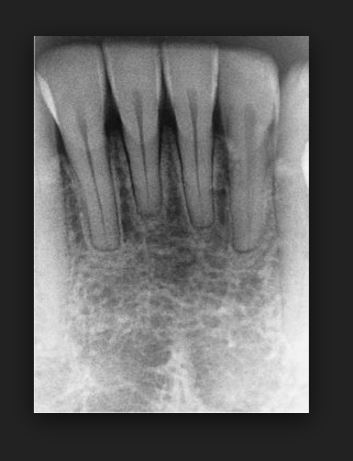

치아교정을 받는 대부분의 환자에서 어느 정도의 치아 뿌리(치근) 흡수 또는 치아 뿌리가 짧아지는 현상이 나타나는데 그 정도가 미미한 정도 1미리에서 1.5미리 정도 라면 큰 문제가 되지 않지만 2미리 이상 치아 뿌리(치근)이 흡수되는 경우에는 정상적인 치아 사용에 문제를 야기시킬 수 있다. 특히 한번 짧아진 치아뿌리(치근)은 다시 길어지는 경우가 극히 드물기 때문에 여러 가지 부작용 중 매우 중요하다고 볼 수 있다.

다른 치아보다 더 흡수가 잘 되는 치아가 있는데 특히 앞니가 이에 속한다. 자연적으로 치아 뿌리는 나쁜 버릇 손가락을 빨거나 손톱을 물어뜯는 나쁜 습관을 장기간 방치하면 앞니 치아 뿌리가 짧아는 현상을 볼 수 있는데 그런 경우 보다 교정시 치아 뿌리 흡수는 더 안 좋은 경우가 많다. 치아가 이동하면서 치아 뿌리 흡수가 일어 날수 일아나면 세심하게 지켜본후 그 정도가 심하면 충치나 나 근관치료등 다른 영향으로 비롯되었는지를 확인한 후 교정치료를 멈추고 신경치료나 충치치료를 한 후 다시 치아교정을 해야 하는 경우도 있으니 교정 후 치아가 많이 흔들리고 뿌리 부분이 너무 아프다고 생각될 때에는 정밀한 검사를 한 후 치아교정을 하는 것이 좋다.